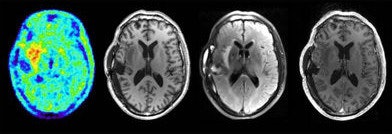

Image T1 MP-RAGE d'une tumeur du cerveau obtenue avec de la F-fluoroethyl-tyrosine (FET) et une image par TEP scanner. Toutes les images sont la propriété de N. Jon Shah, PhD et reproduites avec son accord.

Dans l'étude de l'image d'une tumeur du cerveau, l'utilisation d'un appareil hybride avec du F-fluoroethyl-tyrosene et un IRM à ultra haut champ, a non seulement montré les limites précises de la tumeur, mais a montré aussi comment elle affecte les régions environnantes du cerveau.

Images du cerveau obtenue par IRM pendant une acquisition TEP: TEP FET, T1, T2 combiné, et T1 après injection de contraste.A l'aide de l'IRM à ultra haut champ et l'imagerie TEP du cerveau "le positon vole dans le champ magnétique, et ses mouvements vont être limités à deux directions, et nous devrions améliorer la résolution de la TEP sans aucun coût supplémentaire".